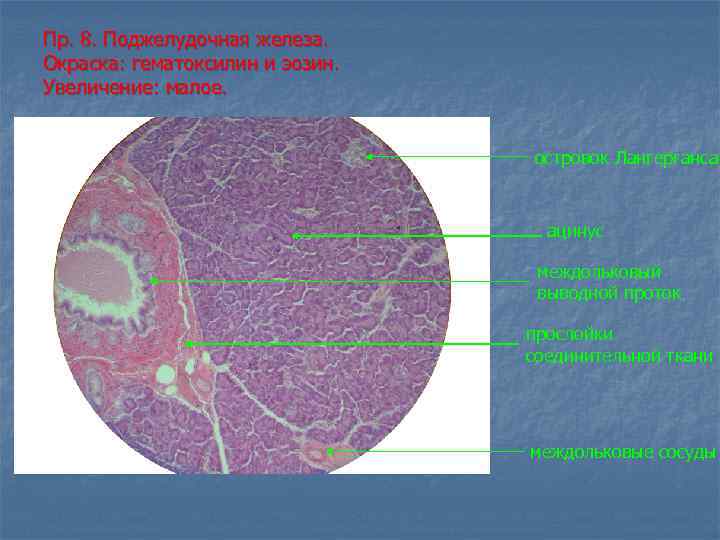

Пр. 8. Поджелудочная железа. Окраска: гематоксилин и эозин. Увеличение: малое. островок Лангерганса ацинус междольковый выводной проток прослойки соединительной ткани междольковые сосуды